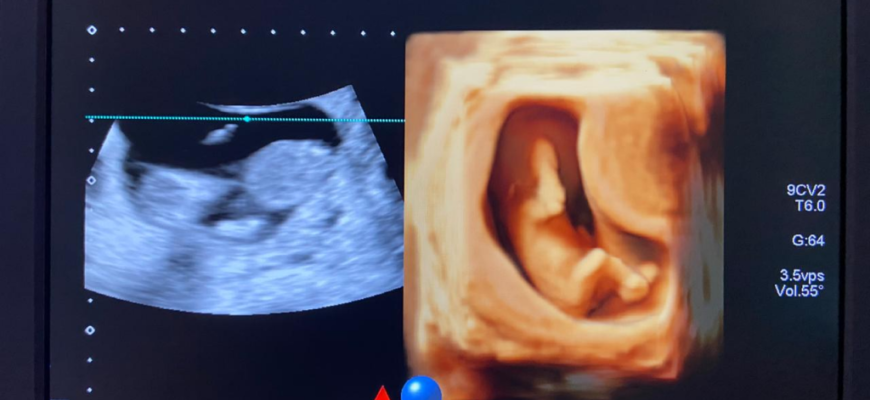

Во время УЗИ в 18 недель можно увидеть, как ваш малыш познает окружающий мир. Он может отражаться в матке от стенки к стенке. Плод ощупывает лицо и сосет большой палец. Все эти моменты прекрасно видны на 3D УЗИ, а при необходимости их можно запечатлеть и сохранить.

На 18 неделе беременности проводят УЗИ второго триместра. В этот период хорошо видны половые органы ребенка. Родители могут узнать пол ребенка, если он не скрывает его половые органы. Иногда определение своего пола откладывают до следующего УЗИ. Организм вашего ребенка начинает вырабатывать миелин (защитное покрытие нервов) с 18-й недели.